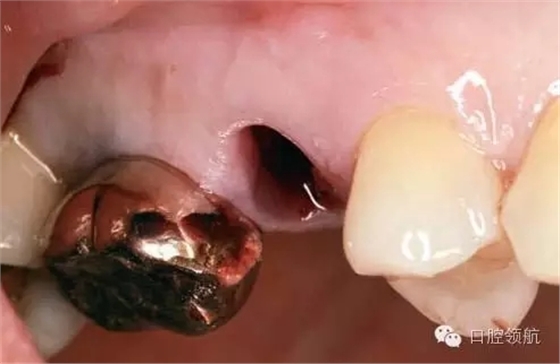

術(shù)前口內(nèi)未見種植體周圍有炎癥等異常表現(xiàn)(圖2),翻開黏骨膜瓣后,10年前手術(shù)入路的痕跡在頰側(cè)骨面已經(jīng)觀察不到了(圖3)。

圖2 ( 左上第五顆牙)拔除后即刻的口內(nèi)像。